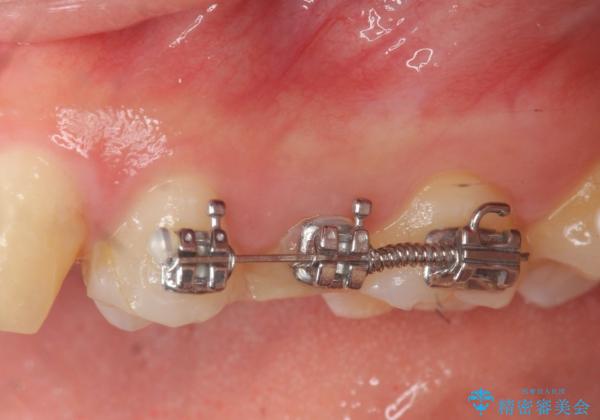

虫歯が大きかったことから、神経の温存はできたものの歯ぐきよりも深い虫歯の問題を解決するため部分矯正治療を併用したセラミック治療を行うこととしました。

当初、歯ぐきよりも深い虫歯のぞんざいや、歯のポジションに問題がありましたがマルチブラケットを用いた部分矯正を行うことで適切な位置へと歯を移動させ、歯周環境を整えたセラミック治療を行うことができました。